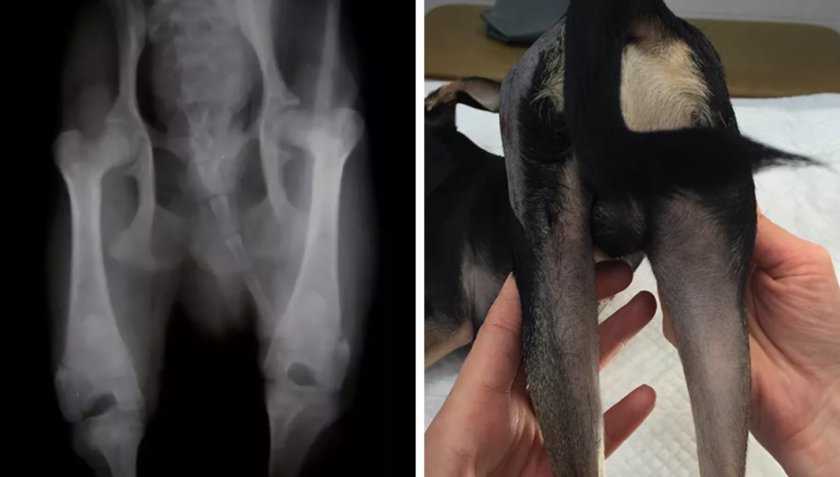

Болезнь Пертеса, рентгенографическое изображение

Йоркширский терьер, болезнь Пертеса обоих тазобедренных суставов, справа разрушение головки бедренной кости, слева проведена артропластика тазобедренного сустава.

При клиническом обследовании собак на позднем этапе развития болезни выявляют, как правило, атрофию мышц бедра (что очень заметно при одностороннем поражении тазобедренного сустава) или обоих бёдер, крепитацию в области сустава из-за нарушения конгруэнтности суставных поверхностей или из-за разрушения головки бедра

У некоторых собак в результате атрофии будет сильно выступать большой вертел бедренной кости, это важно от дифференцировать ветеринарному врачу от вывиха

В большинстве случаев для подтверждения диагноза достаточно проведения рентгенографического исследования тазобедренного сустава в вентродорсальной проекции. Если у собаки очень сильная болезненность, то возможно проведения седации, для того чтобы не травмировать излишне и так больной сустав. На ранних этапах болезни на рентгенографическом изображении головки и шейки бедра будут видны увеличение плотности кости, изменение формы головки бедра в следствии ишемического некроза и изменение внутрисуставного пространства. На более поздних этапах болезни Пертеса на рентгенографическом изображении будут видны признаки остеоартроза, остеофиты в результате разрушения головки бедра в области вертлужной впадины, в некоторых случаях хорошо видна линия патологического перелома шейки бедра.